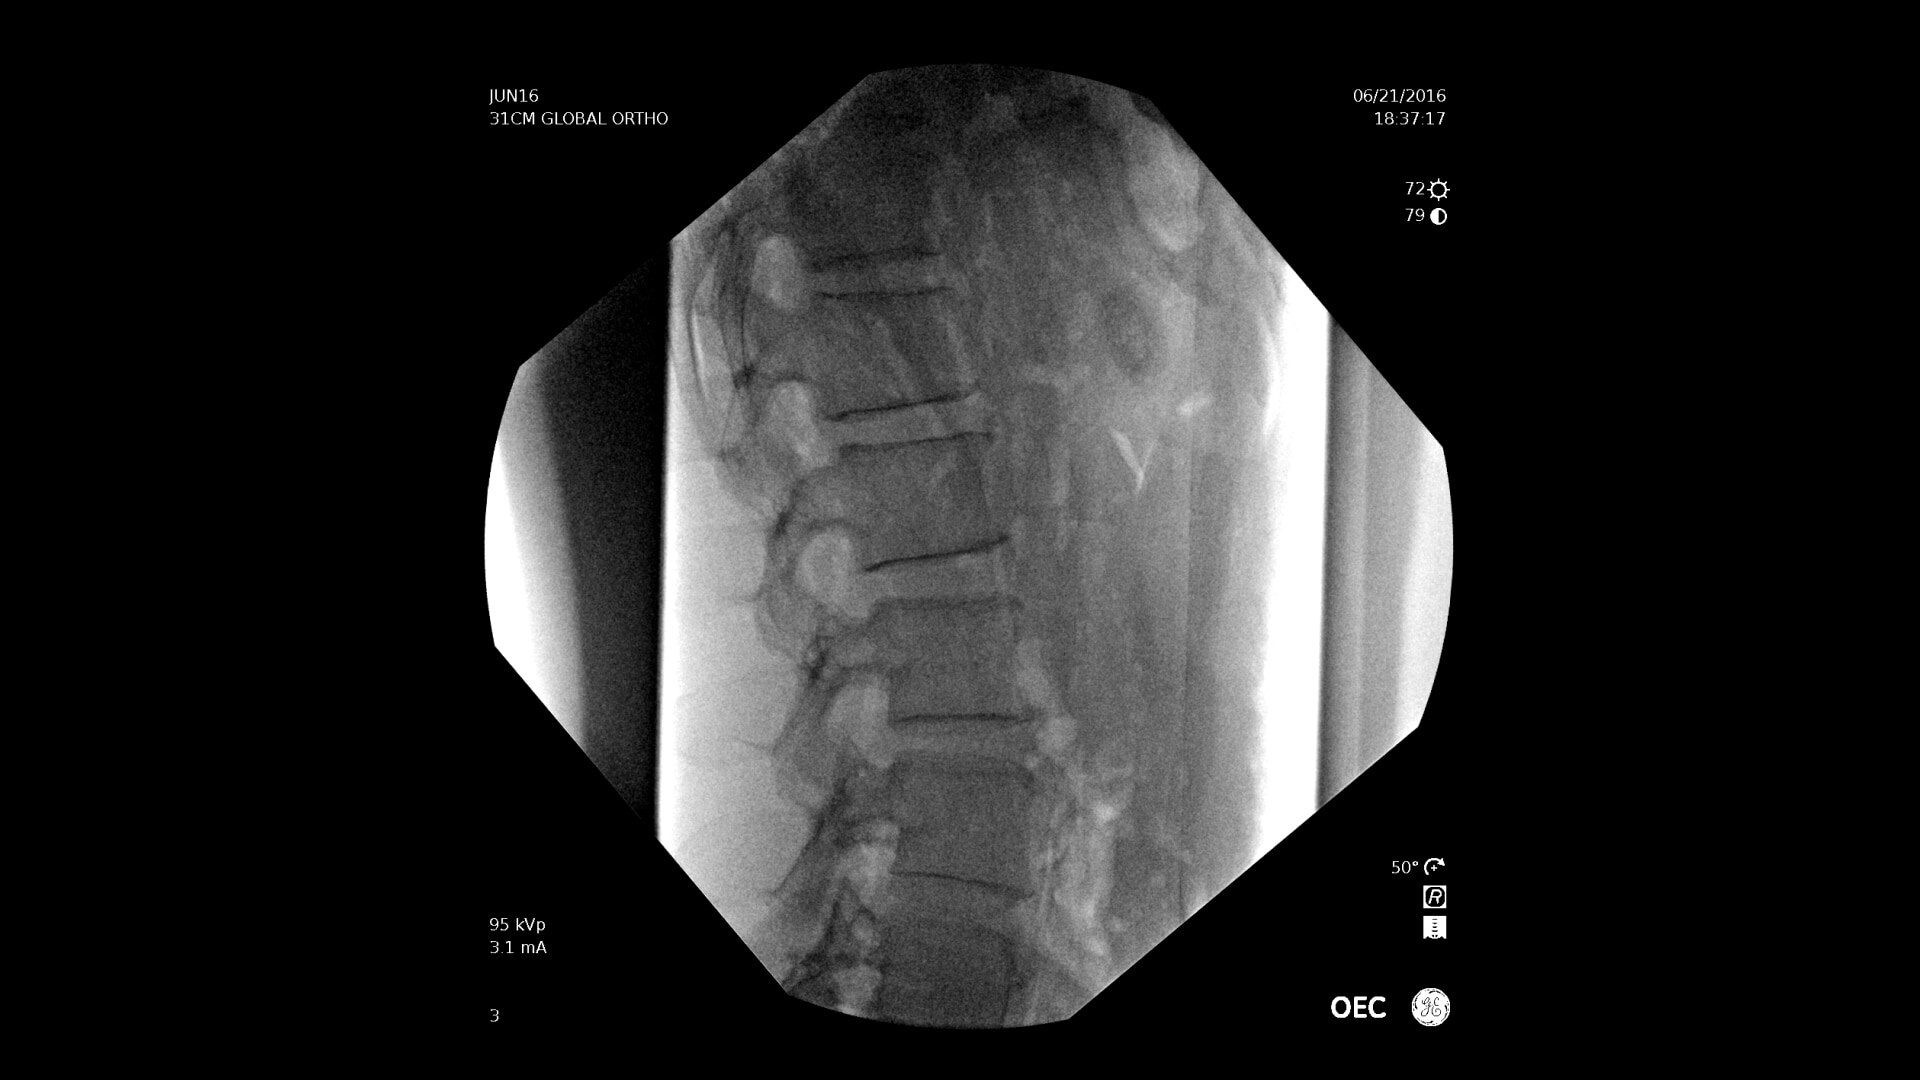

Consistently experience amazing image quality, precision, and efficiency during simple to complex pain management procedures with OEC C-arms.

Achieve precision and efficiency while experiencing the image quality needed during simple to complex pain management procedures with OEC C-arms.

See clear detail captured on a flat panel detector to a 4K display for visualization of anatomical detail.

With choice of C-arms to fit a variety of needs, easily obtain challenging spine angles with a 55° overscan, rainbows without moving the base, or a motorized drive.

OEC C-arms perform imaging in a variety of procedures such as:

• Thoracolumbar procedures